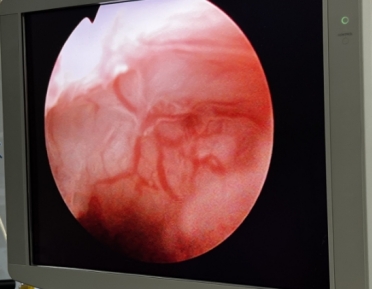

宮腔鏡下可見疤痕憩室處血管充盈